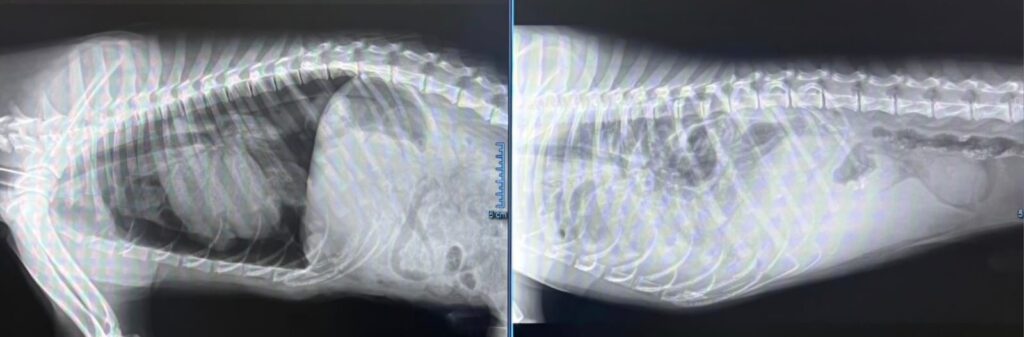

La diagnosi è nefasta: grave ernia diaframmatica che ha provocato lo spostamento di tutti gli organi all’interno del torace. Dovuto ad un trauma, probabilmente Angelo veniva preso a calci da piccolino quando viveva in strada, prima che lo trovassimo noi.

Angelo è stato operato. L’intervento in emergenza durato due ore, è riuscito. Gli organi sono stati rimessi a posto ed ora è vigile e reattivo . Dobbiamo aspettare che trascorrano 48 ore per dire se è davvero fuori pericolo ma i medici veterinari sono fiduciosi! Ora è nella terapia intensiva costantemente monitorato.